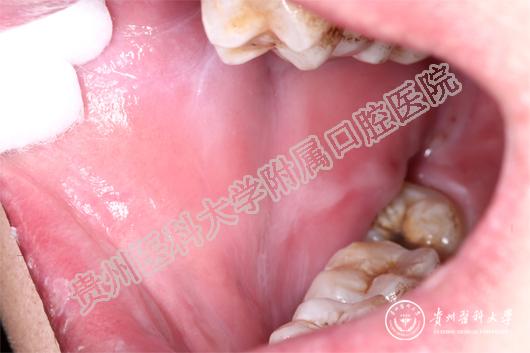

(患者治疗前后的口腔黏膜病损对比 上图:治疗前,下图:治疗1周后)

当天值班的王珣主治医师为小邓这一特殊病人加号,并作了相关检查后诊断小邓为药物引起的“过敏性口炎”。王珣介绍:小邓来的时候已经很严重了,上下唇、手背、拇指已经出现红色斑块,并且全口黏膜溃烂、生殖器可见不规则糜烂面。像小邓这种情况根本无法进食、而且疼痛难忍。若不及时救治,很有可能造成电解质紊乱。随后王珣医生询问病史发现:原来,5天前,小邓因智齿冠周炎自行服用了“消炎片”,随后出现全口黏膜溃烂,无法进食而且说话都困难,随后皮肤上也起红斑,生殖器也开始溃烂,疼痛难耐,无法入睡,人也明显消瘦了许多。

王珣叮嘱患者停用可疑药物,并为他对症用药。由于“过敏性口炎”的病情发展变化较大,王珣医生还为患者留了自己的微信,以便实时了解小邓的病情变化。1周后,小邓复诊时口腔生殖器黏膜已经痊愈,上下唇及手背、拇指的斑块也基本消退。小邓非常感谢beat365唯一官方网站附属口腔医院,在疫情的特殊时期能为他开通绿色通道,让他的疾病痊愈 。